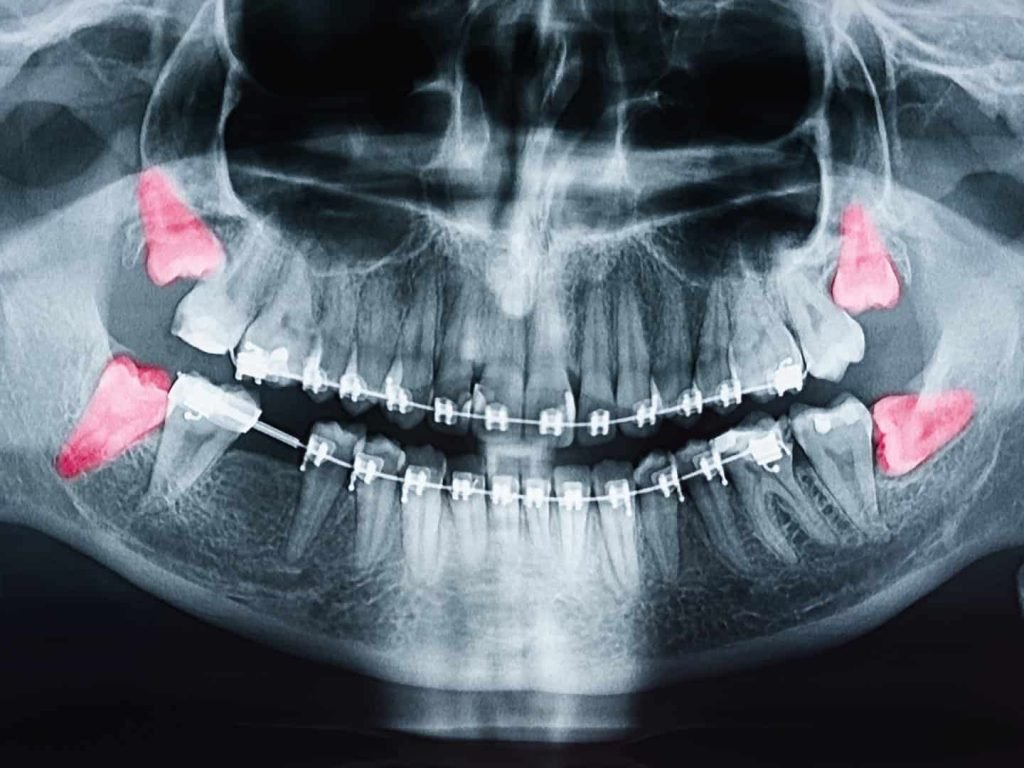

Impacted or Problematic Teeth

Teeth that are trapped beneath the gums or growing at an angle, such as wisdom teeth, may require surgical removal to prevent pain, swelling, or crowding.

Orthodontic Preparation

In some cases, removing specific teeth creates space for alignment treatments. This ensures better long-term results when planning orthodontic care.